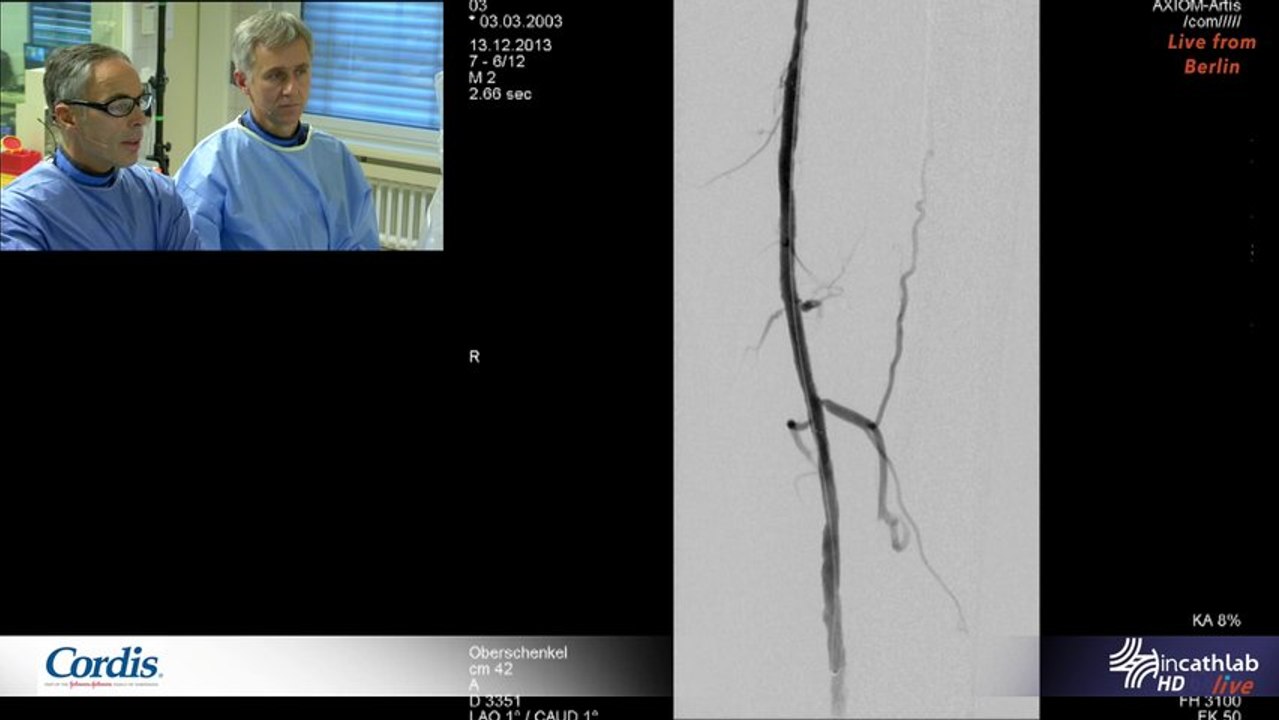

A New Stent Design to overcome complex SFA anatomies

Live From Berlin , Sankt Gertrauden Krakenhaus